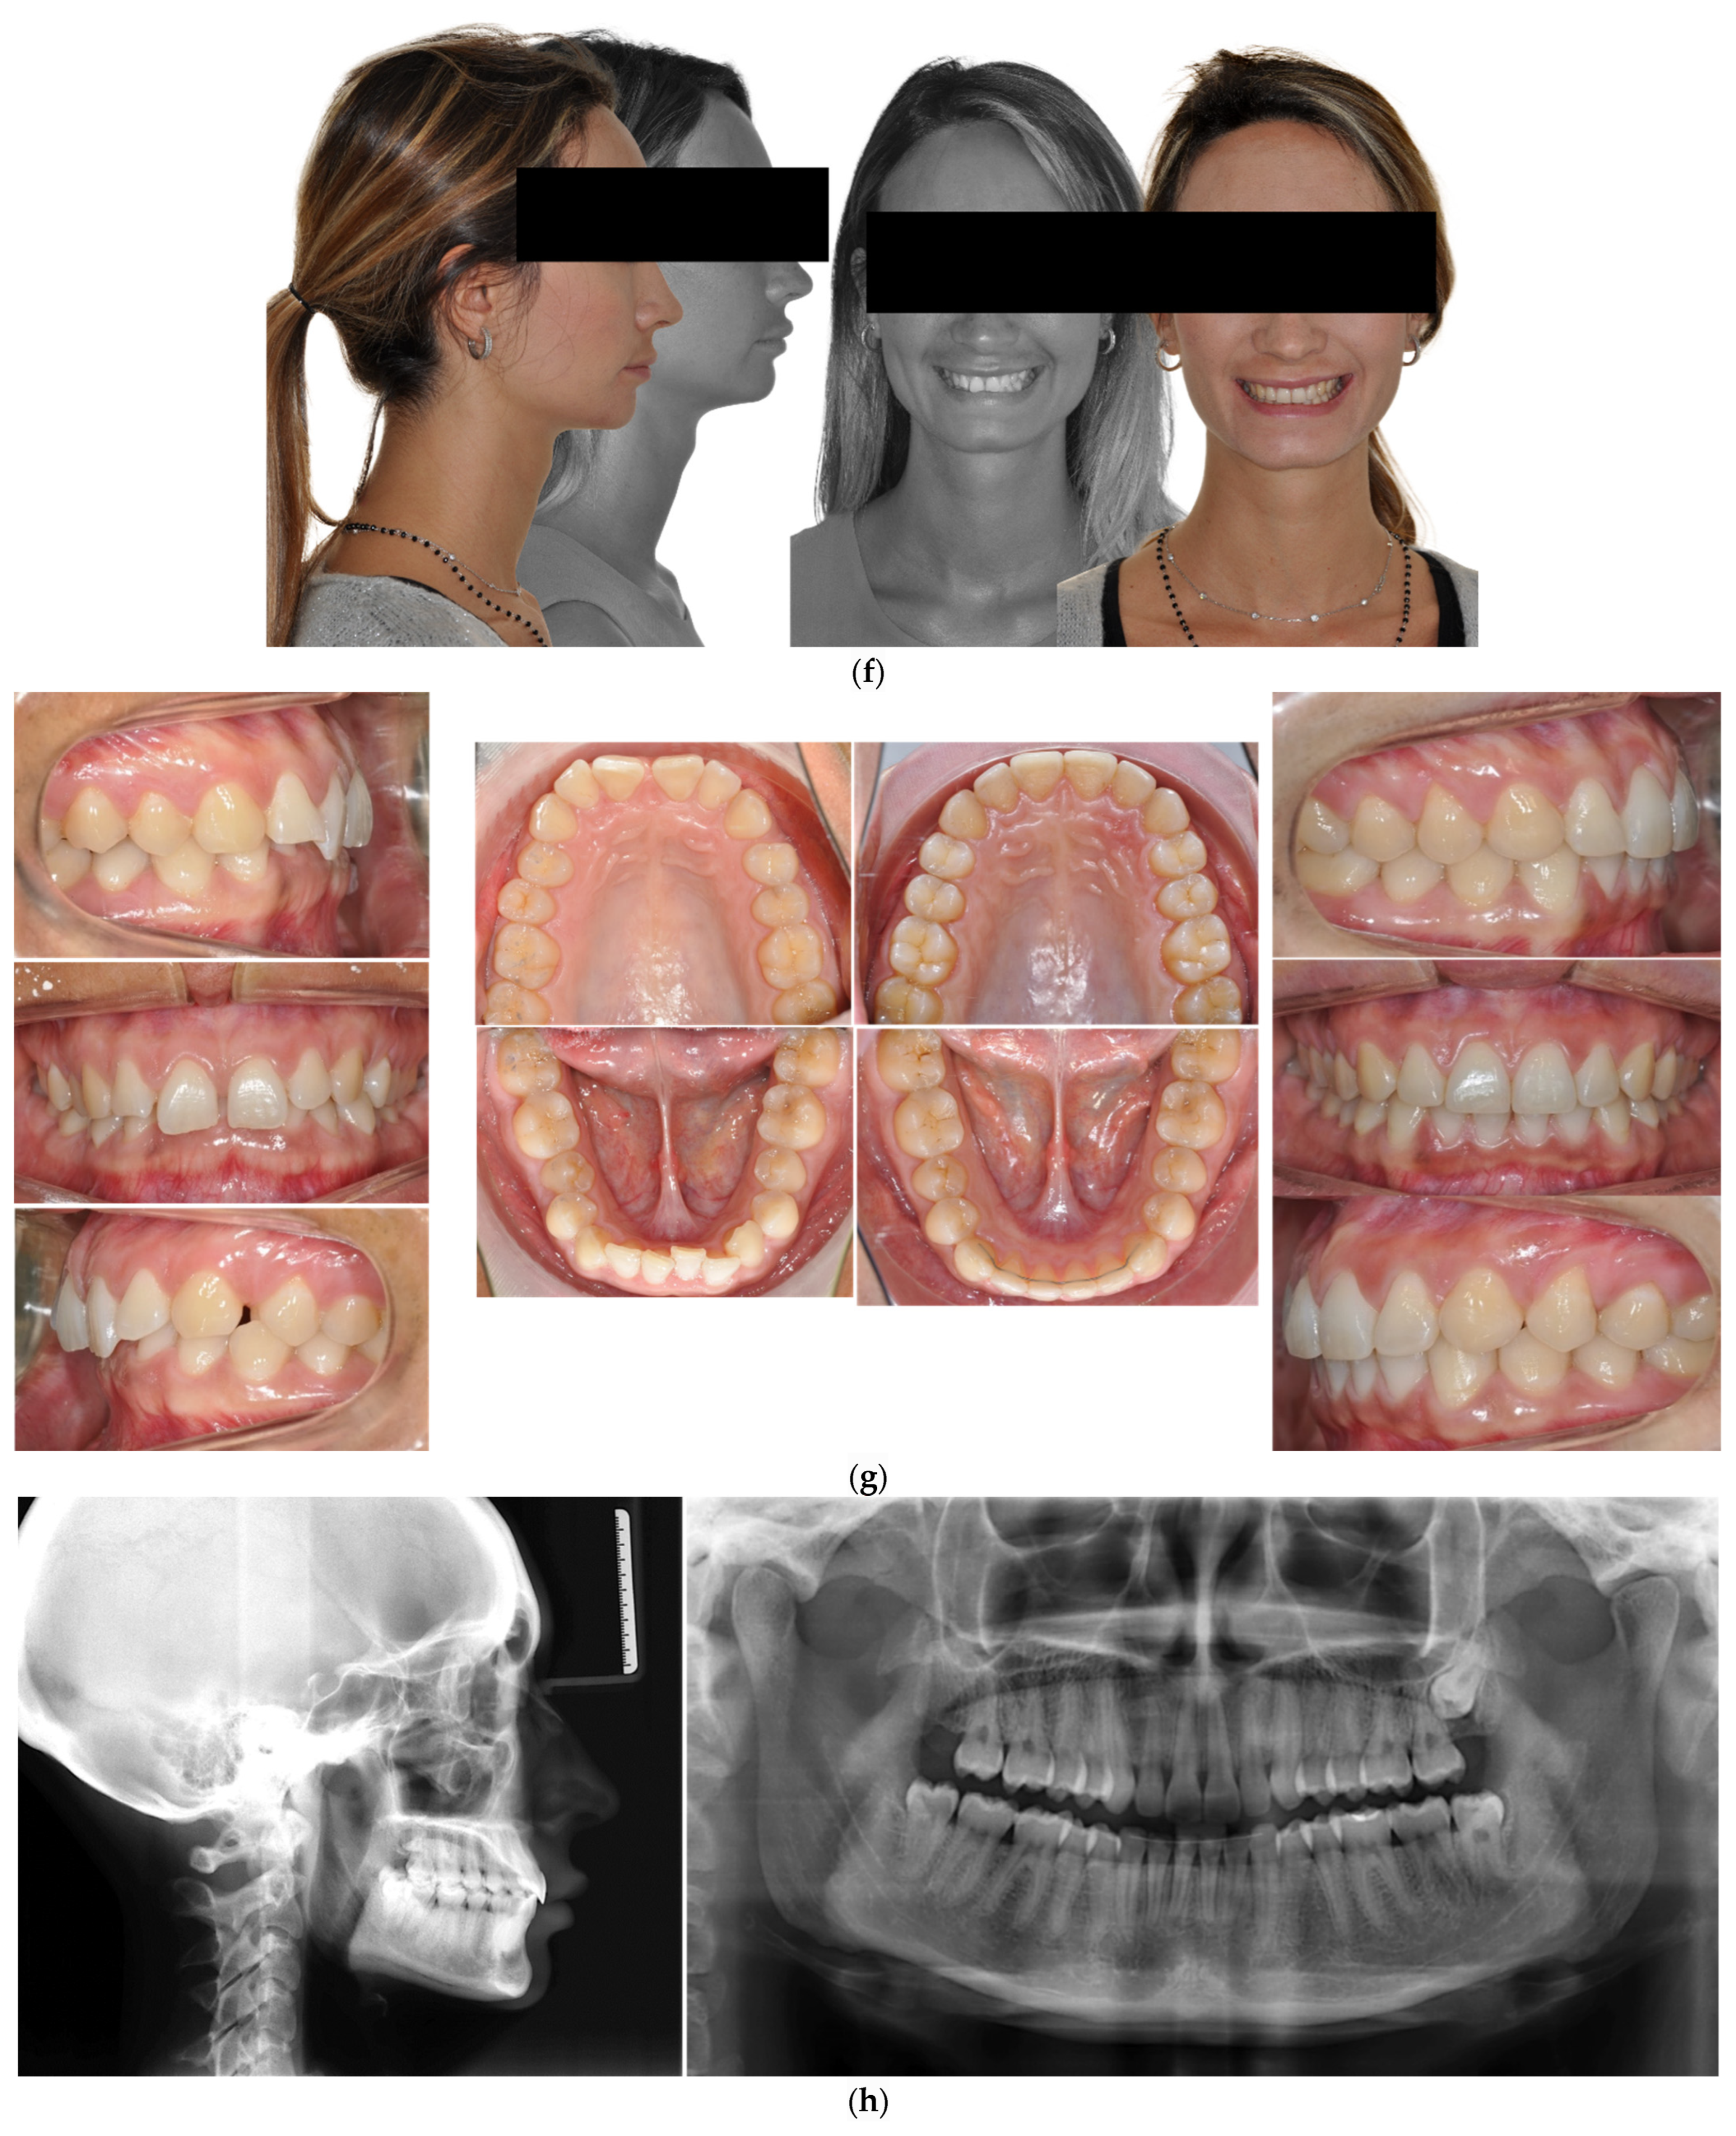

The patient was a 32-year-old female seeking orthodontic treatment due to aesthetic reasons. She presented a straight profile with reduced lower facial height. Her occlusal relationship was a Class III malocclusion, and there were black corridors in both arches with microdontia of the upper laterals. She also presented a deep bite without palatal impingement (Figure 4).

Figure 4.

(a,b) The initial images of the profile and frontal smile view and intraoral images and radiographs, including panoramic radiographs and a lateral cephalogram. (c) The digital setup performed for the treatment. (d) The treatment in progress with the aligners and lingual appliances. (e–g) Post-treatment images and a comparison with the initial images. (h) shows a superimposition of the pre- and post-treatment cephalograms.

The treatment objectives were to resolve the Class III malocclusion, achieving a Class I canine and molar relationship, close the spaces, eliminate the deep bite and improve the facial profile. The treatment plan chosen was clear aligners in the upper jaw and a lingual appliance in the lower jaw plus IPR. The upper arch was treated only with a series of nine clear aligners and a bite ramp, while the lower was fitted with the Alias PSL lingual system with the following archwire sequence: 0.014- and 0.016-inch CuNiti for levelling and alignment; 0.016 × 0.016-inch and 0.018 × 0.018-inch CuNiTi for rotational, tip and torque control; and 0.0175 × 0.0175-inch TMA for detailing.

The treatment duration was ten months, upon which a removable retention was prescribed for the upper arch and a lingual fixed retention with a passive 0.012 NiTi wire from 33 to 43 was fitted in the lower arch.

A similar strategy was used in Case 2 (Figure 4), but in that case, the challenge was rotation of 33 and space closure while maintaining a good root position. An upper aligner with a bite ramp was therefore used to create a bite-plane effect, helping to open the initial deep bite and enhance the flattening of the curve of Spee via the lingual appliance. The facial profile was preserved as the incisor torque was well-controlled with the lingual appliances. In this case, the advantage of using a hybrid approach was again to keep the treatment time short (approximately 10 months). Aligners produce a bowing effect during space closure, creating a lateral open bite, but this was well-controlled using lingual appliances due to the rigidity of the archwire. The tipping of upper incisors due to an aligner corresponds to the drawbridge effect, which is amply explained in the literature [33,37]. The intermolar width was maintained at 54 mm in the upper arch and 46 mm in the lower arch.